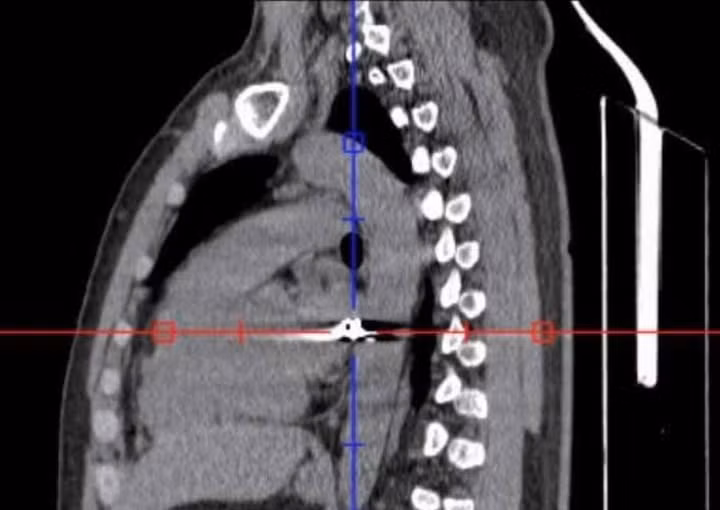

Qua thăm khám ban đầu, các bác sĩ xác định viên đạn đi theo đường phức tạp từ vùng lưng phải xuyên qua lồng ngực sang bên trái – khu vực tập trung nhiều cơ quan trọng yếu như tim, phổi và các mạch máu lớn, đe dọa trực tiếp đến tính mạng người bệnh.

Sau hơn 4 giờ phẫu thuật căng thẳng, các bác sĩ đã kiểm soát được tổn thương, đồng thời gắp thành công một đầu đạn có kích thước khoảng 0,3 x 0,5 cm ra khỏi cơ thể bệnh nhân.

Đạn bắn xuyên ngực - Ảnh BVCC